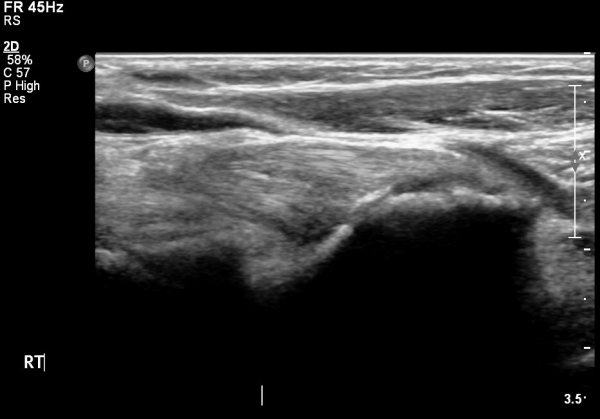

ŽÃËÀÚ¸¦ ¸»´ÜºÎ·Î À̵¿ÇÏ´Ï ¿ä°ñµ¶±â ÀÌµÎ¹Ú±Ù°Ç ÂøºÎ¿¡¼­ °ÏÀÌ Àú¿¡ÄÚ ºÎÁ¾ »óÅ·Π°üÂûµÇ°í(»çÁø 2)